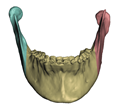

2.5.1. Bones

- Segmentation of the maxilla and mandible. For all patients, the highest error (except for the neck, which is not clinically relevant as discussed above) appears near the cut areas, both of the maxilla (e.g., patients M5 and M7) and the mandible (e.g., patients M1 and M3). This is probably due to the presence of fixation plates and/or bone grafts in the real result (e.g., patient M10, whose maxilla was not segmented, but where the presence of bone graft has been confirmed by the surgeon who carried out the intervention). As a consequence, patients with a segmented maxilla and/or mandible show in general larger error than those without segmented bones. However, the smooth coupling method proposed in Section 2.3.3 reduces considerably the error in cut areas, as shown in Figure 2.